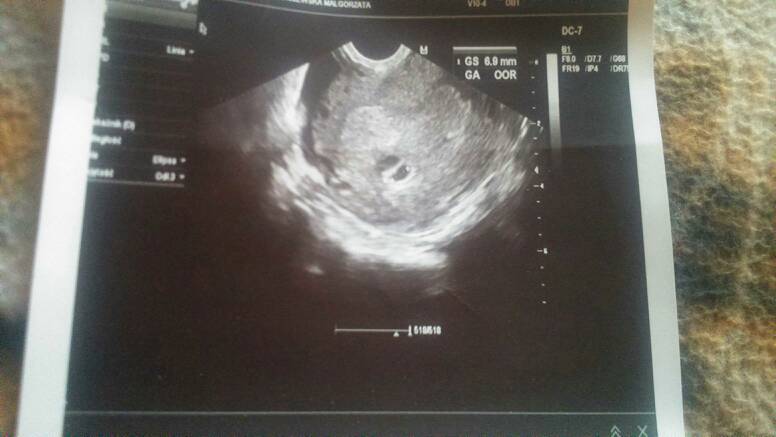

Takie coś mam tylko:( i się jakoś niepokoje

• 1458920285881.jpg

1458920285881.jpg

32,4 KB · Wyświetleń: 90